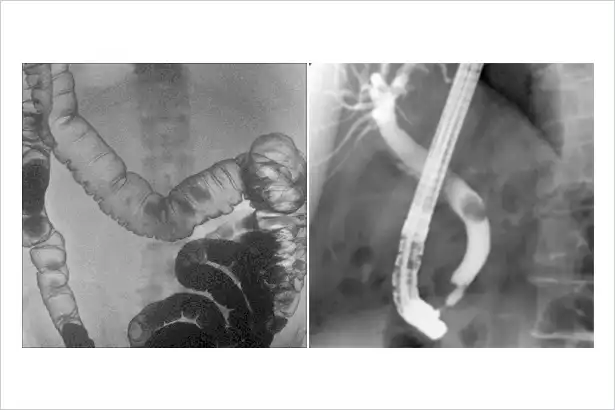

胃肠系统临床图像

介入治疗临床图像